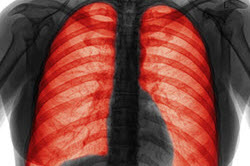

什么是慢性阻塞性肺病?

慢性阻塞性肺病或COPD是指一組導(dǎo)致氣流阻塞和呼吸相關(guān)問題的疾病。它包括肺氣腫和慢性支氣管炎。